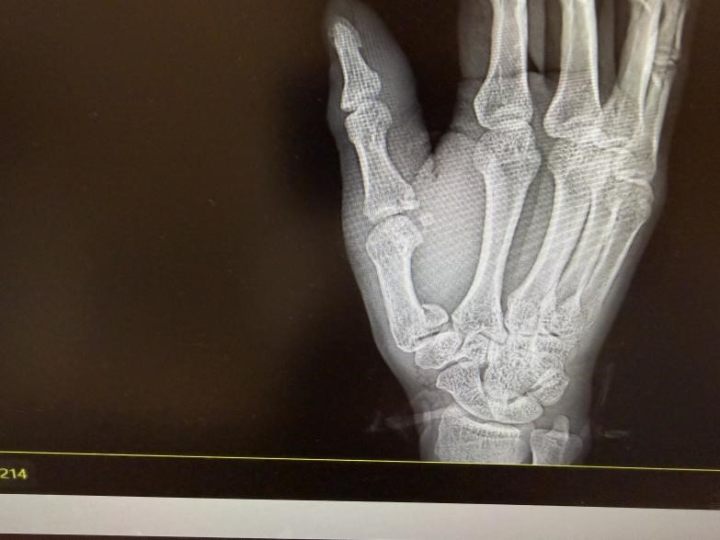

拍片结果印证了刘医生的判断,李先生右手第一掌骨、第一近节指骨基底部都骨折了。刘医生为他的伤口做了清创缝合,随后骨科医生也及时介入,做了临时石膏固定,后续李先生还得住院择期手术。